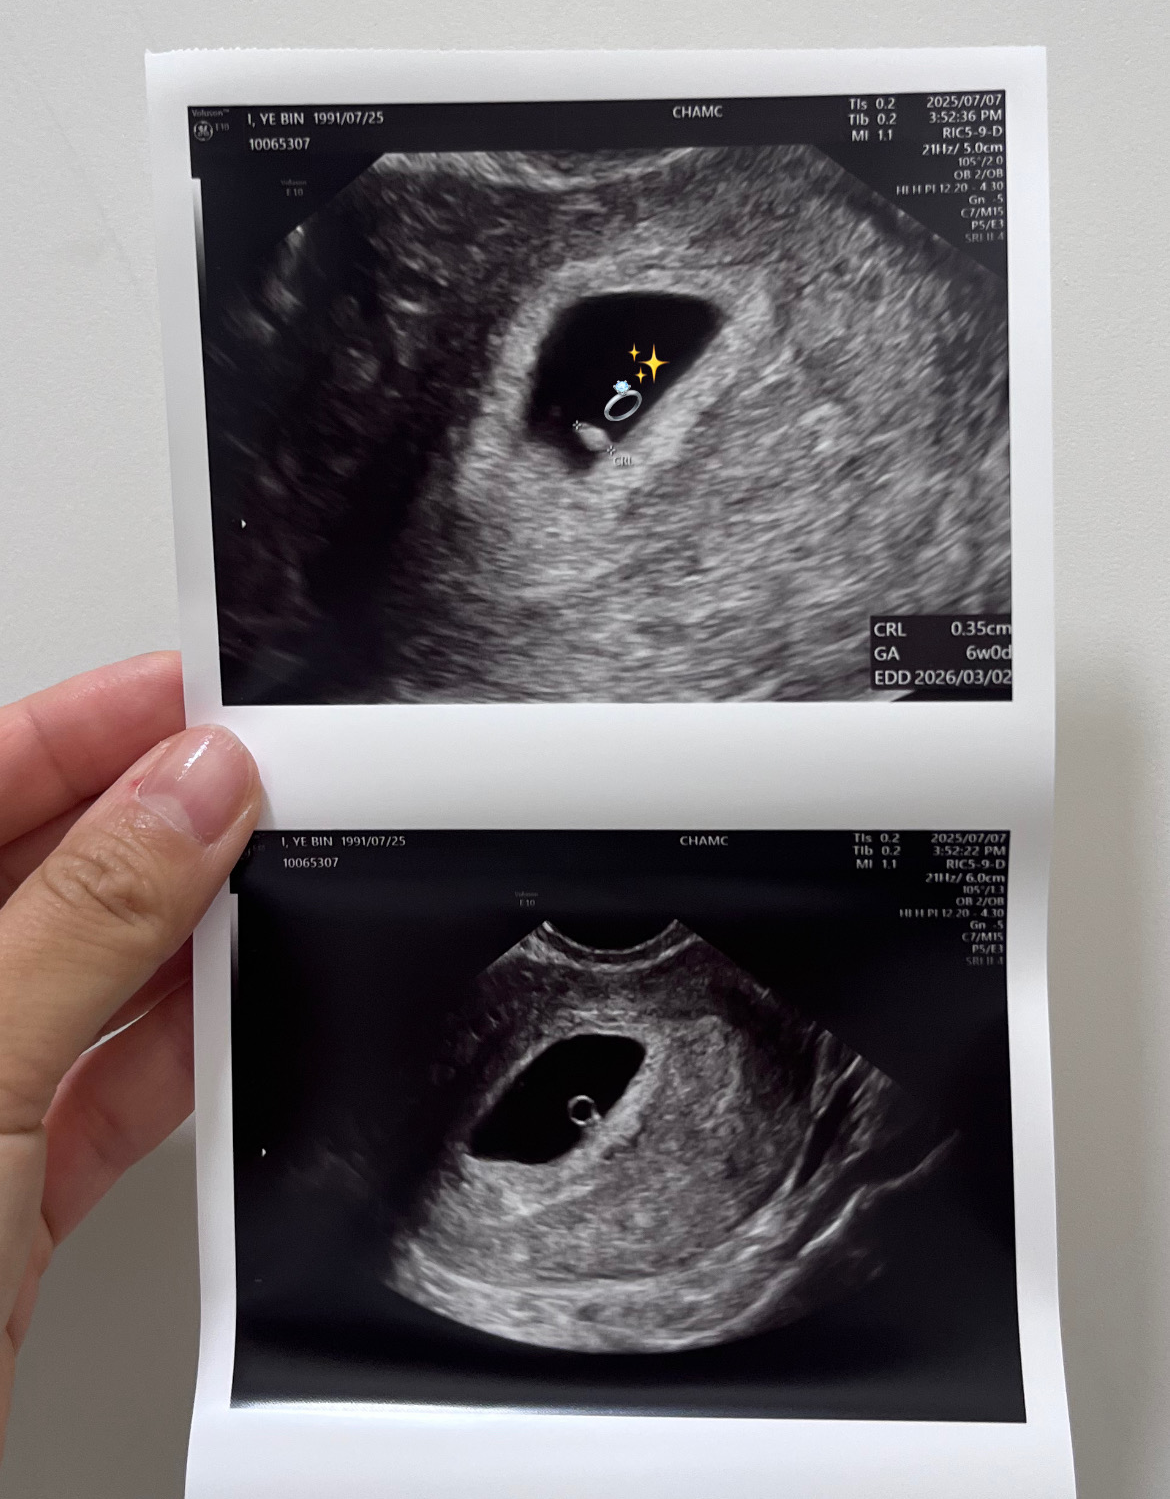

6주차에 만난 완주는 난황도 동그랗고 선명했고 심장 뛰는 것도 보여줬다. 너무나도 감격스러웠다.. 내 몸에 심장이 두 개라니.. 심장 뛰는 게 깜빡깜빡 거려서 사람들이 다이아몬드 확인했다고 표현을 하는데 왜 그런지 이해가 됐다. 흑흑.. 이렇게 잘 자라느라고 입덧이 심하구나.. 오케.. 엄마 오케이.. 참아볼게